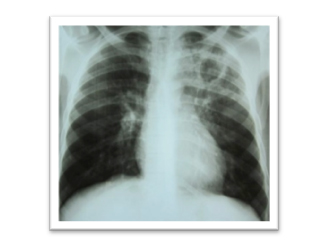

Tuberculosis is infectious disease cause by bacteria called ‘Mycobacterium tuberculosis’. It most commonly involves lungs. It can also involve lymph nodes, abdomen, brain and other organs. Its very common in India.